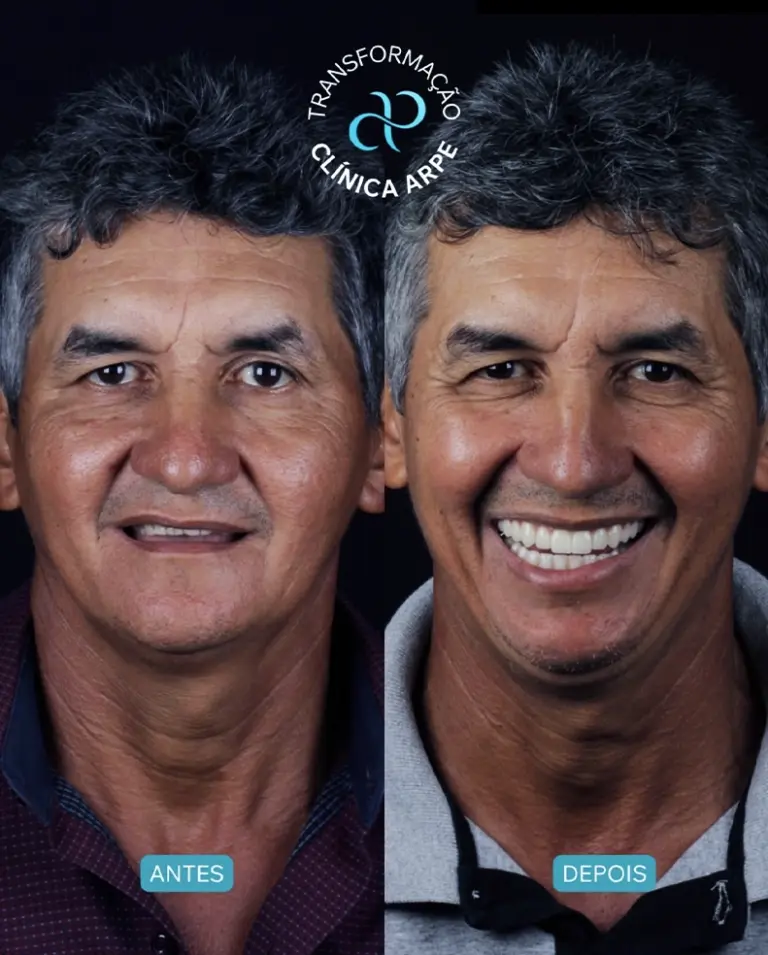

O Implante Dentário é o tratamento mais moderno e eficiente para substituir algum dente perdido, reestabelecendo função e estética. O pino do implante substitui a raiz do dente e suporta a prótese sobre implante, devolvendo a anatomia desejada.

Os implantes podem ser unitários e devolver a estrutura de um dente perdido, ou múltiplos servindo de suporte para próteses totais ou parciais, eliminando a necessidade de uso de próteses removíveis que geram certo desconforto e insegurança ao paciente.

O Implantodontista busca superar as limitações de cada caso através de um planejamento individualizado. Utilizamos tecnologia e materiais biocompatíveis para dar ao paciente uma melhor e mais rápida eficiência mastigatória e um sorriso agradável.

O Implantodontista irá avaliar as alterações funcionais, entender o que te incomoda no seu sorriso e na sua mordida, avaliar clinicamente a região que irá receber o implante e o volume ósseo presente. Em seguida, solicita os exames pré-tratamento cirúrgico, incluindo radiografias, tomografias, fotografias e escaneamento intra-oral

Através dos exames e das informações colhidas na primeira consulta, o especialista consegue realizar o planejamento reverso e apresentar ao paciente a programação dos implantes necessários para a resolução do caso, se há necessidade de enxerto ósseo, qual tipo de implante é o mais indicado para ele

As orientações em relação a medicação e cuidados são passadas previamente ao procedimento. Quando o implante instalado fica aderido mecanicamente ao osso (chamamos de torque de resistência do implante contra o osso) podemos inserir sobre o implante um dente provisório ou definitivo imediatamente após a cirurgia. Chamamos esse caso de “carga imediata”. Quando não temos essa aderência mecânica no momento da cirurgia, é necessário aguardar de 90 a 150 dias para que tenhamos uma adesão do implante ao osso, e aí sim instalar a coroa provisória ou definitiva